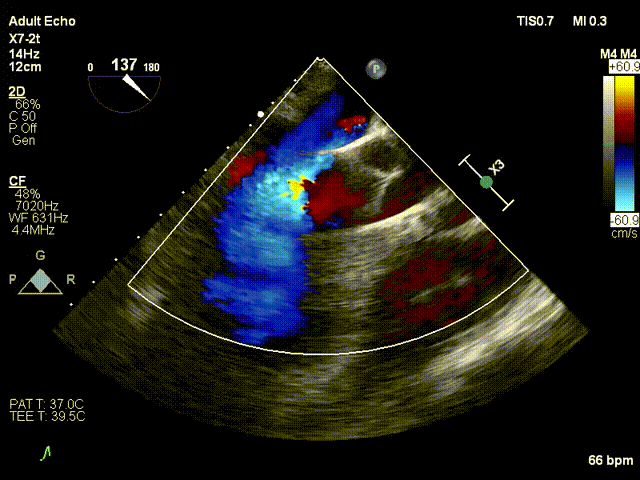

彩色多普勒探及主动脉瓣重度反流、二尖瓣轻度反流、三尖瓣微量反流血流。

术前超声

术后超声